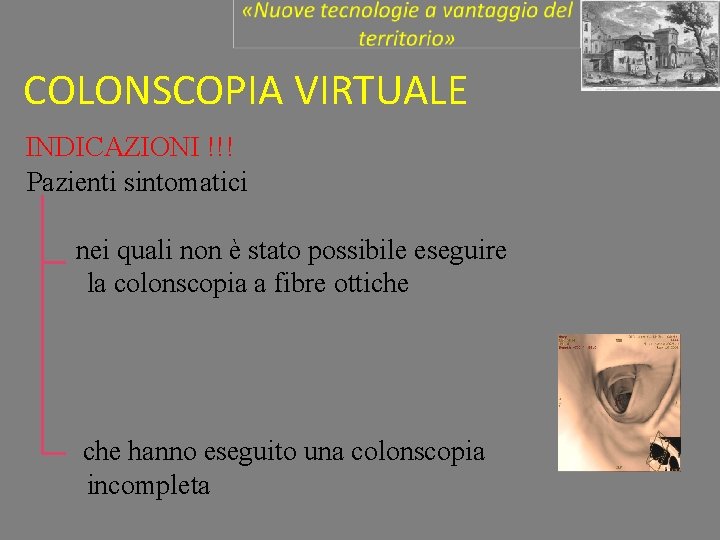

COLONSCOPIA VIRTUALE INDICAZIONI !!! Pazienti sintomatici nei quali non è stato possibile eseguire la colonscopia a fibre ottiche hanno eseguito una colonscopia incompleta